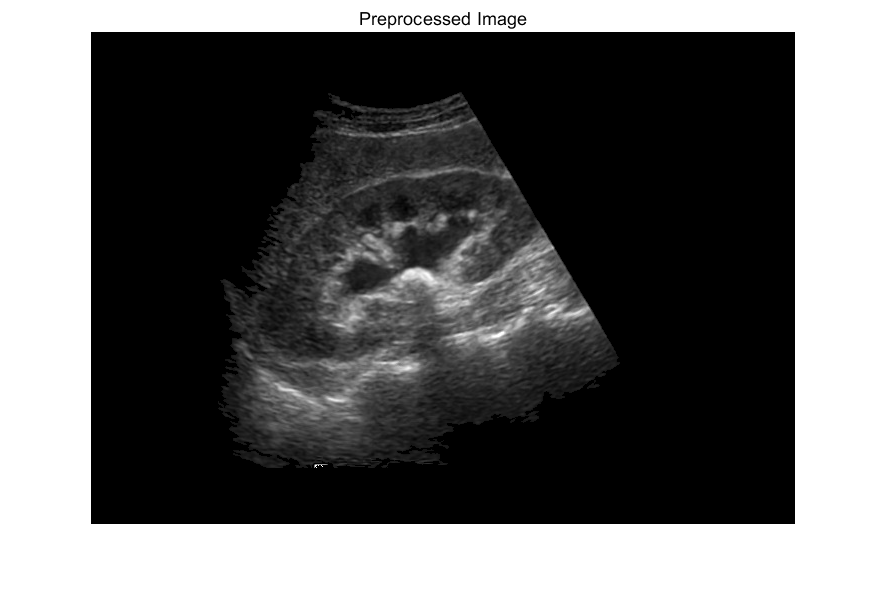

%% Image Preprocessing phase

%Converting into grayscale image && %% Getting pixel info

gray_image=rgb2gray(original_image); %a and b

figure;

imshow(gray_image),title('Grayscale Image');

impixelinfo %Give pixel intensity of any [x,y] data coordinates